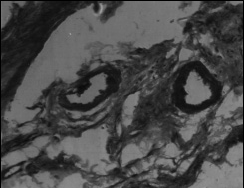

Эпителиальный покров. При гистологическом исследовании препаратов всех групп были выявлены изменения со стороны эпителиального покрова. Они более выражены в лакунах, меньше на зевной поверхности и зависели в значительной мере от длины и ветвистости крипт. Принято, что признаком хронического тонзиллита является значительная ретикуляция эпителия, т.е. разрастание ретикулярной сети в эпителии и обильную инфильтрацию ее лимфоцитами и плазматическими клетками. В наших наблюдениях при токсическом зобе инфильтрация лимфоцитами достигала такой степени, что граница между эпителием и подлежащей тканью перестает определяться (рис.1,2). В некоторых наблюдениях в эпителиальном покрове обнаруживались единичные полиморфноядерные лейкоциты в эпителии крипт, а также папиллярные выросты стенок крипт (рис.3), закрывающие их просвет и тем самым создающие условия для задержки содержимого крипт. Как известно, в развитии хронического тонзиллита .особое значение придается задержке отделяемого крипт. В результате наличия ветвистых извилистых крипт, папиллярных выростов, пробки приводят к сужению и даже полной облитерации устьев крипт (рис.4,5). Задержка со-держимого крипт в отдельных случаях обусловливает расширение их просвета (рис.6), а при полной облитерации некоторые авторы наблюдали образование ретенционных кист (рис.7).

Рис. 1. Лимфоидно-клеточная инфильтрация эпителия. Окраска гематоксилин-эозин, ув. х 400 |

Рис. 2. Граница между эпителием и подлежащей тканью стерта. Окраска гематоксилин- эозин, ув. х 400 |